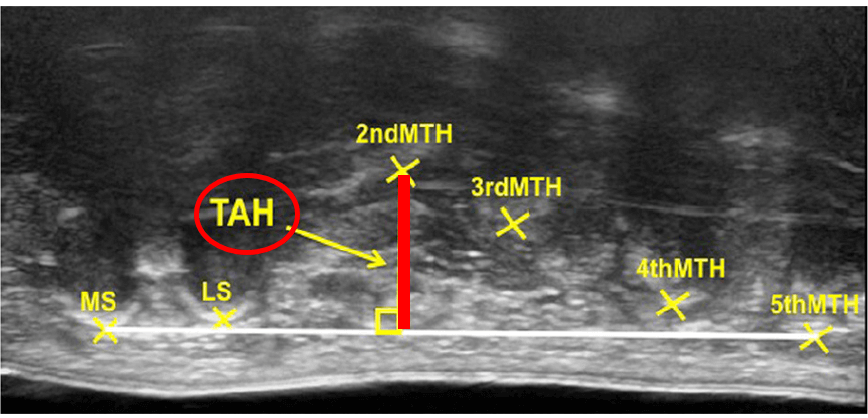

1. 橫弓高度(Transverse arch height, TAH) 為第二蹠骨頭(2nd MTH)與內側種子骨(Medial sesamoid bone, MS)到第五蹠骨頭之垂直距離 (下圖粗紅線)

此圖為足部冠狀切面,由腳趾頭往足跟的方向看 (由前往後的方向)